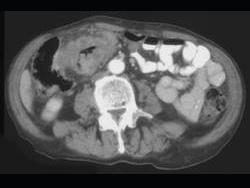

问题 男,45岁,右下腹胀痛、并可触及质硬包块,请结合图像选择最可能诊断 ( )

选项 A、结肠淋巴瘤 B、慢性溃疡性结肠炎 C、结肠癌 D、肠结核 E、结肠crohn病

答案 C